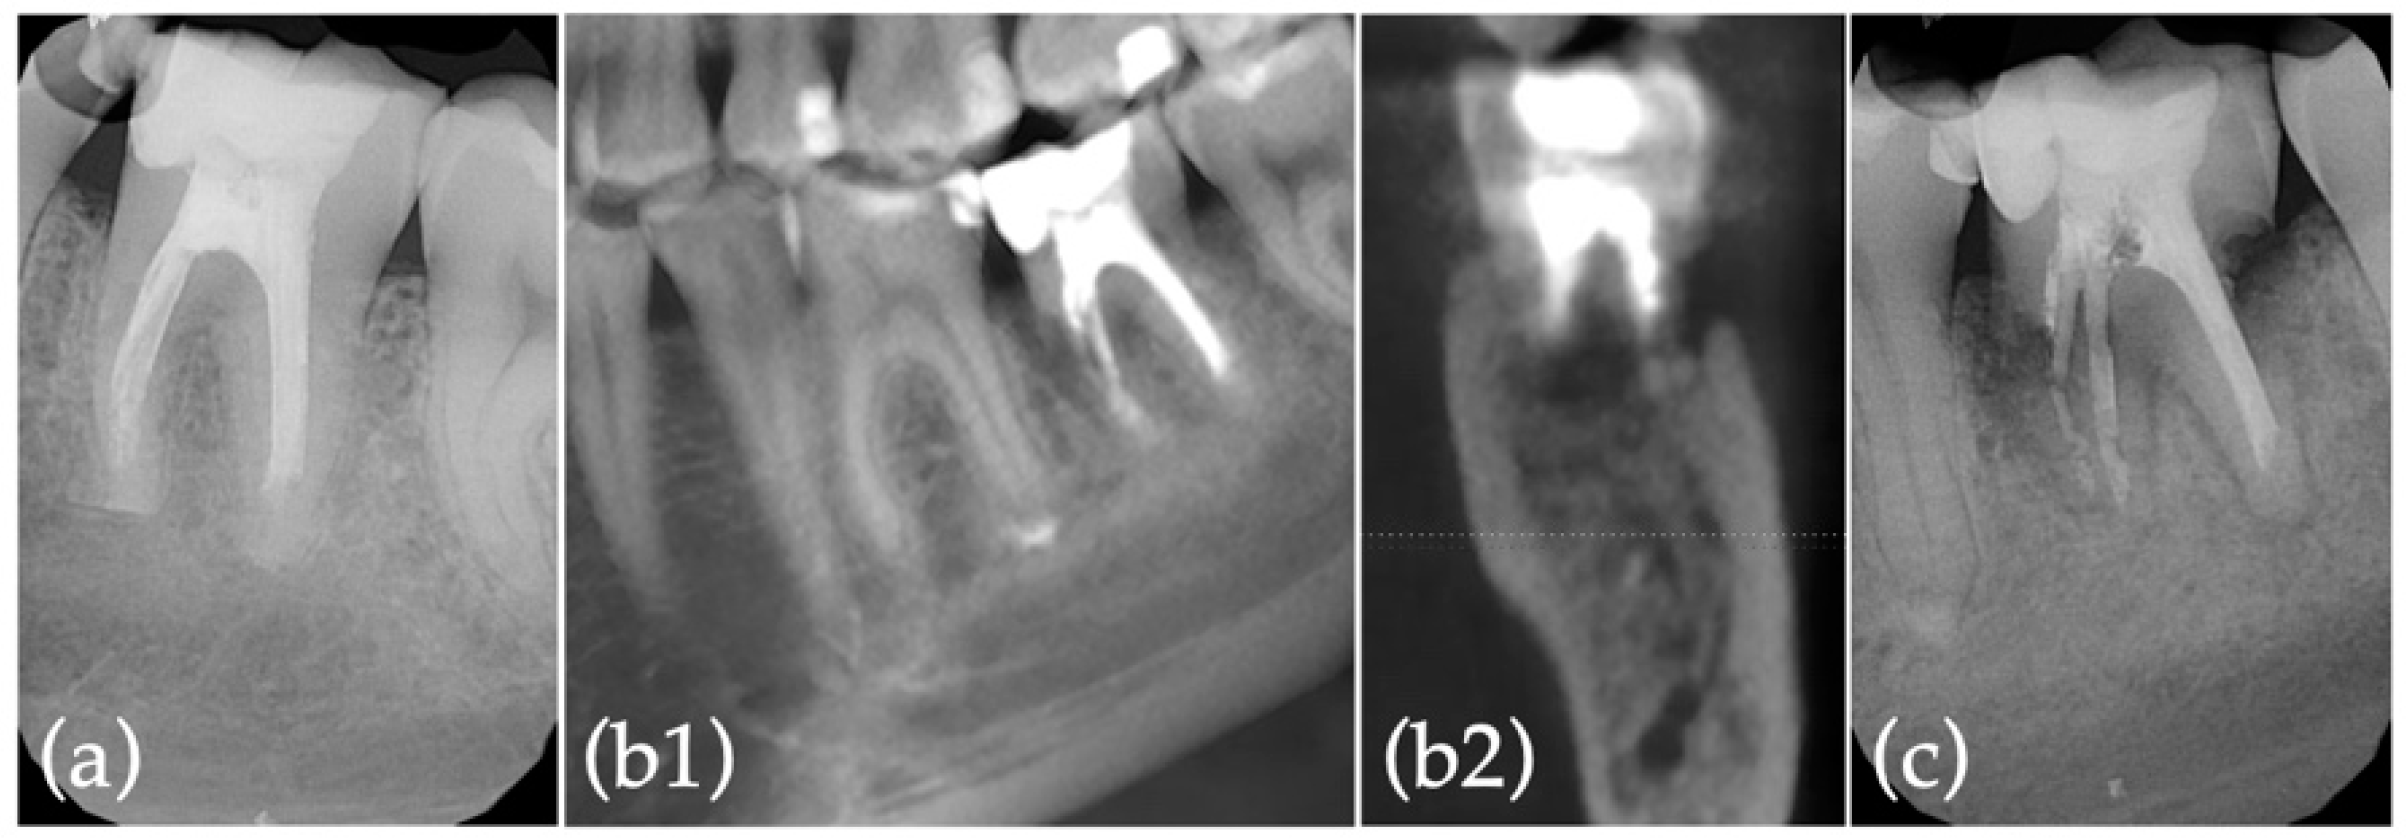

2.2. Extraction with Alveolar Ridge Preservation Using Leukocyte-Platelet Rich Fibrin (L-PRF)

2.3. Implant Surgery